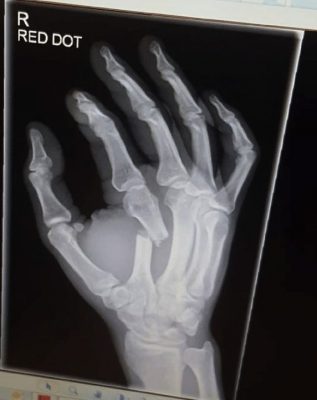

The x-ray he posted on his social media this evening confirmed that he suffered a devastating fracture.

The caption stated:

“Well my friends… I am proud of my performance and so should my opponent Peter. He truly rose to the occasion and put on a fantastic performance. I assume you all want to see the broken hand X rays lol… Well… here you go! It is hard to believe I fought a whole nother round with this thing busted like this still punching and grabbing with it lol. Praise God for adrenaline!”